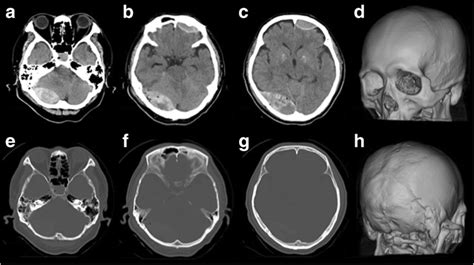

Skull Fracture with Parenchymal and Subdural Brain Hematomas

Skull Fracture with Parenchymal and Subdural Brain Hematomas from anatomicaljustice.com